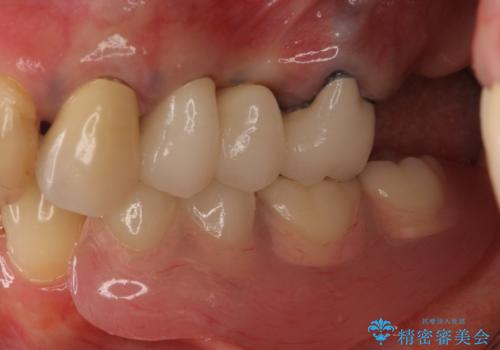

患者様はインプラント等の外科処置は希望されなかったため、セラミックと義歯で治療を行いました。

義歯を製作する際は、支えとなる歯の治療も同時に行うことで、義歯の製作が容易になります。

今回もそのように製作したところ、適合がよく安定のよい義歯になりました。患者様本人も使っていて全く痛くないとのことで、追加の調整もなく使用して頂いてます。患者様には、大変満足して頂きました。